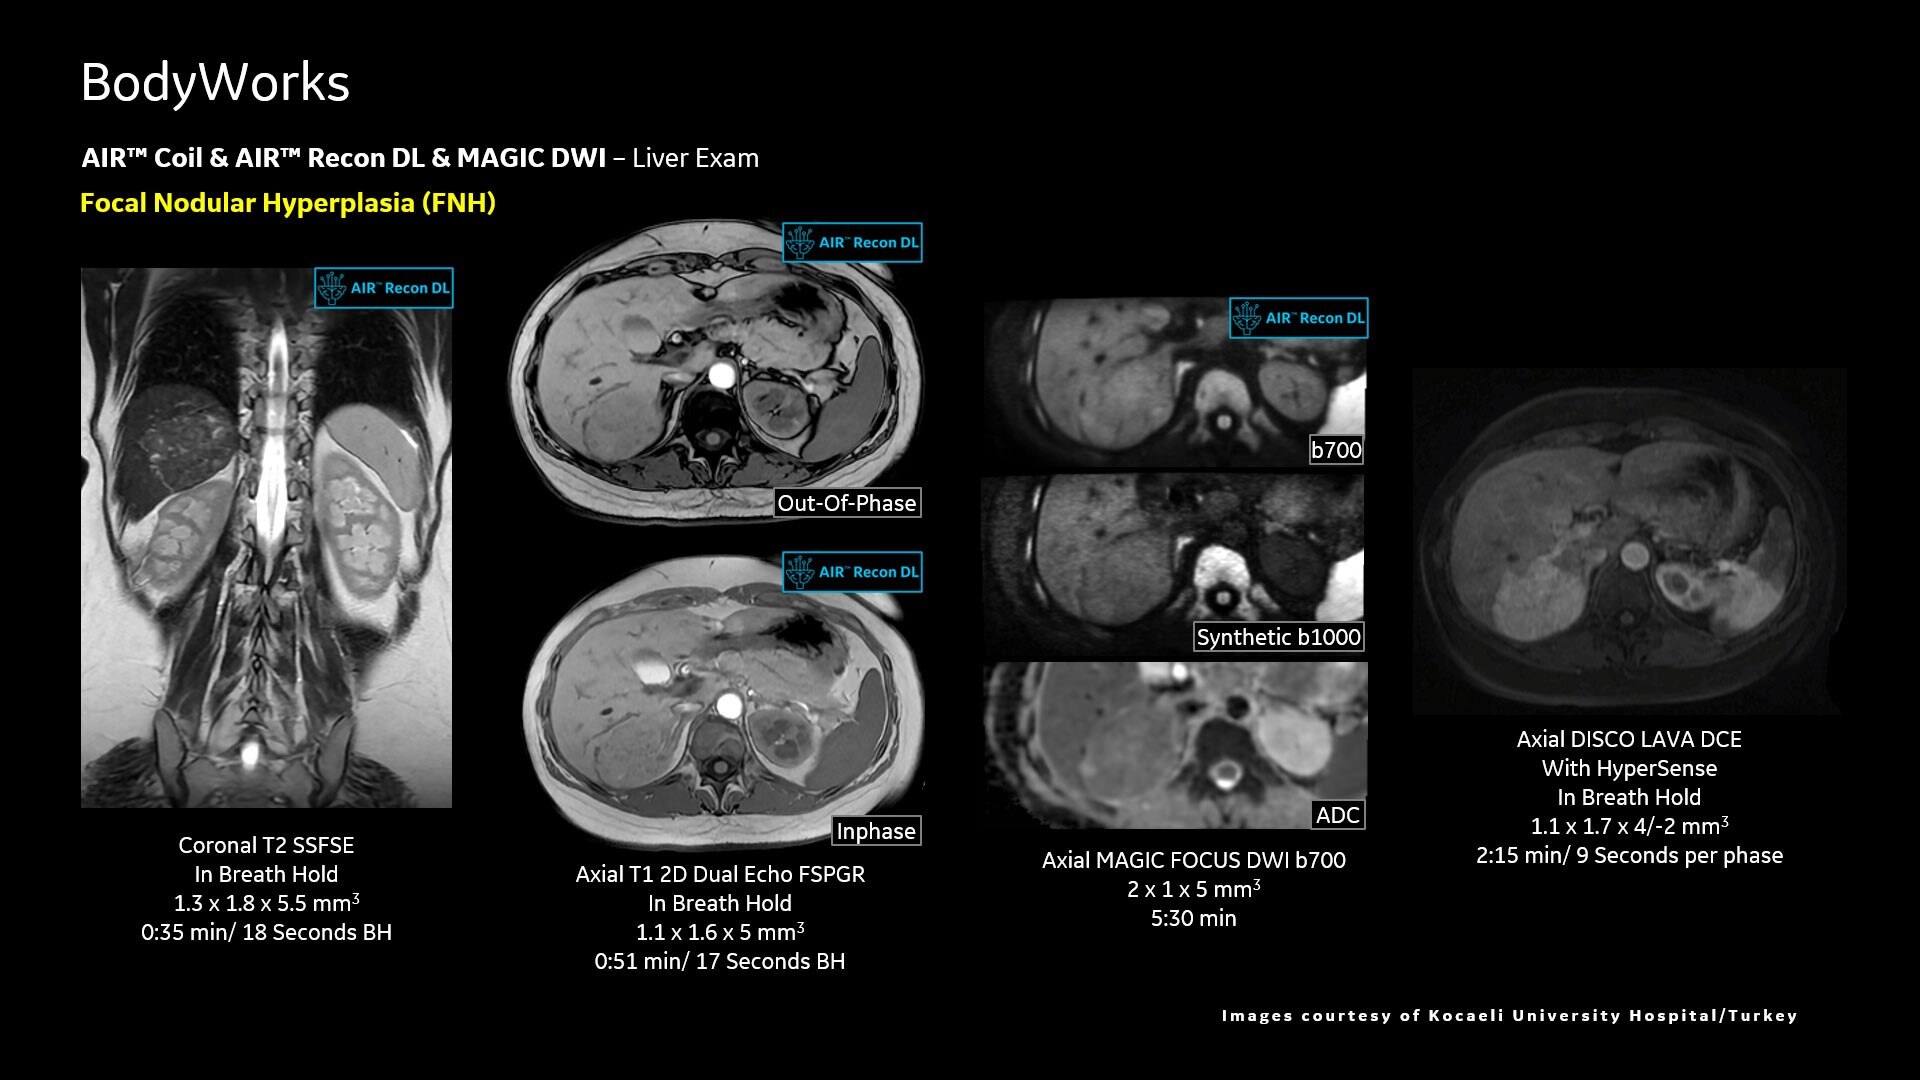

AIR™ Recon DL improves SNR and image sharpness, enabling shorter scan times

Up to 50% faster acquisition time with AIR™ Recon DL